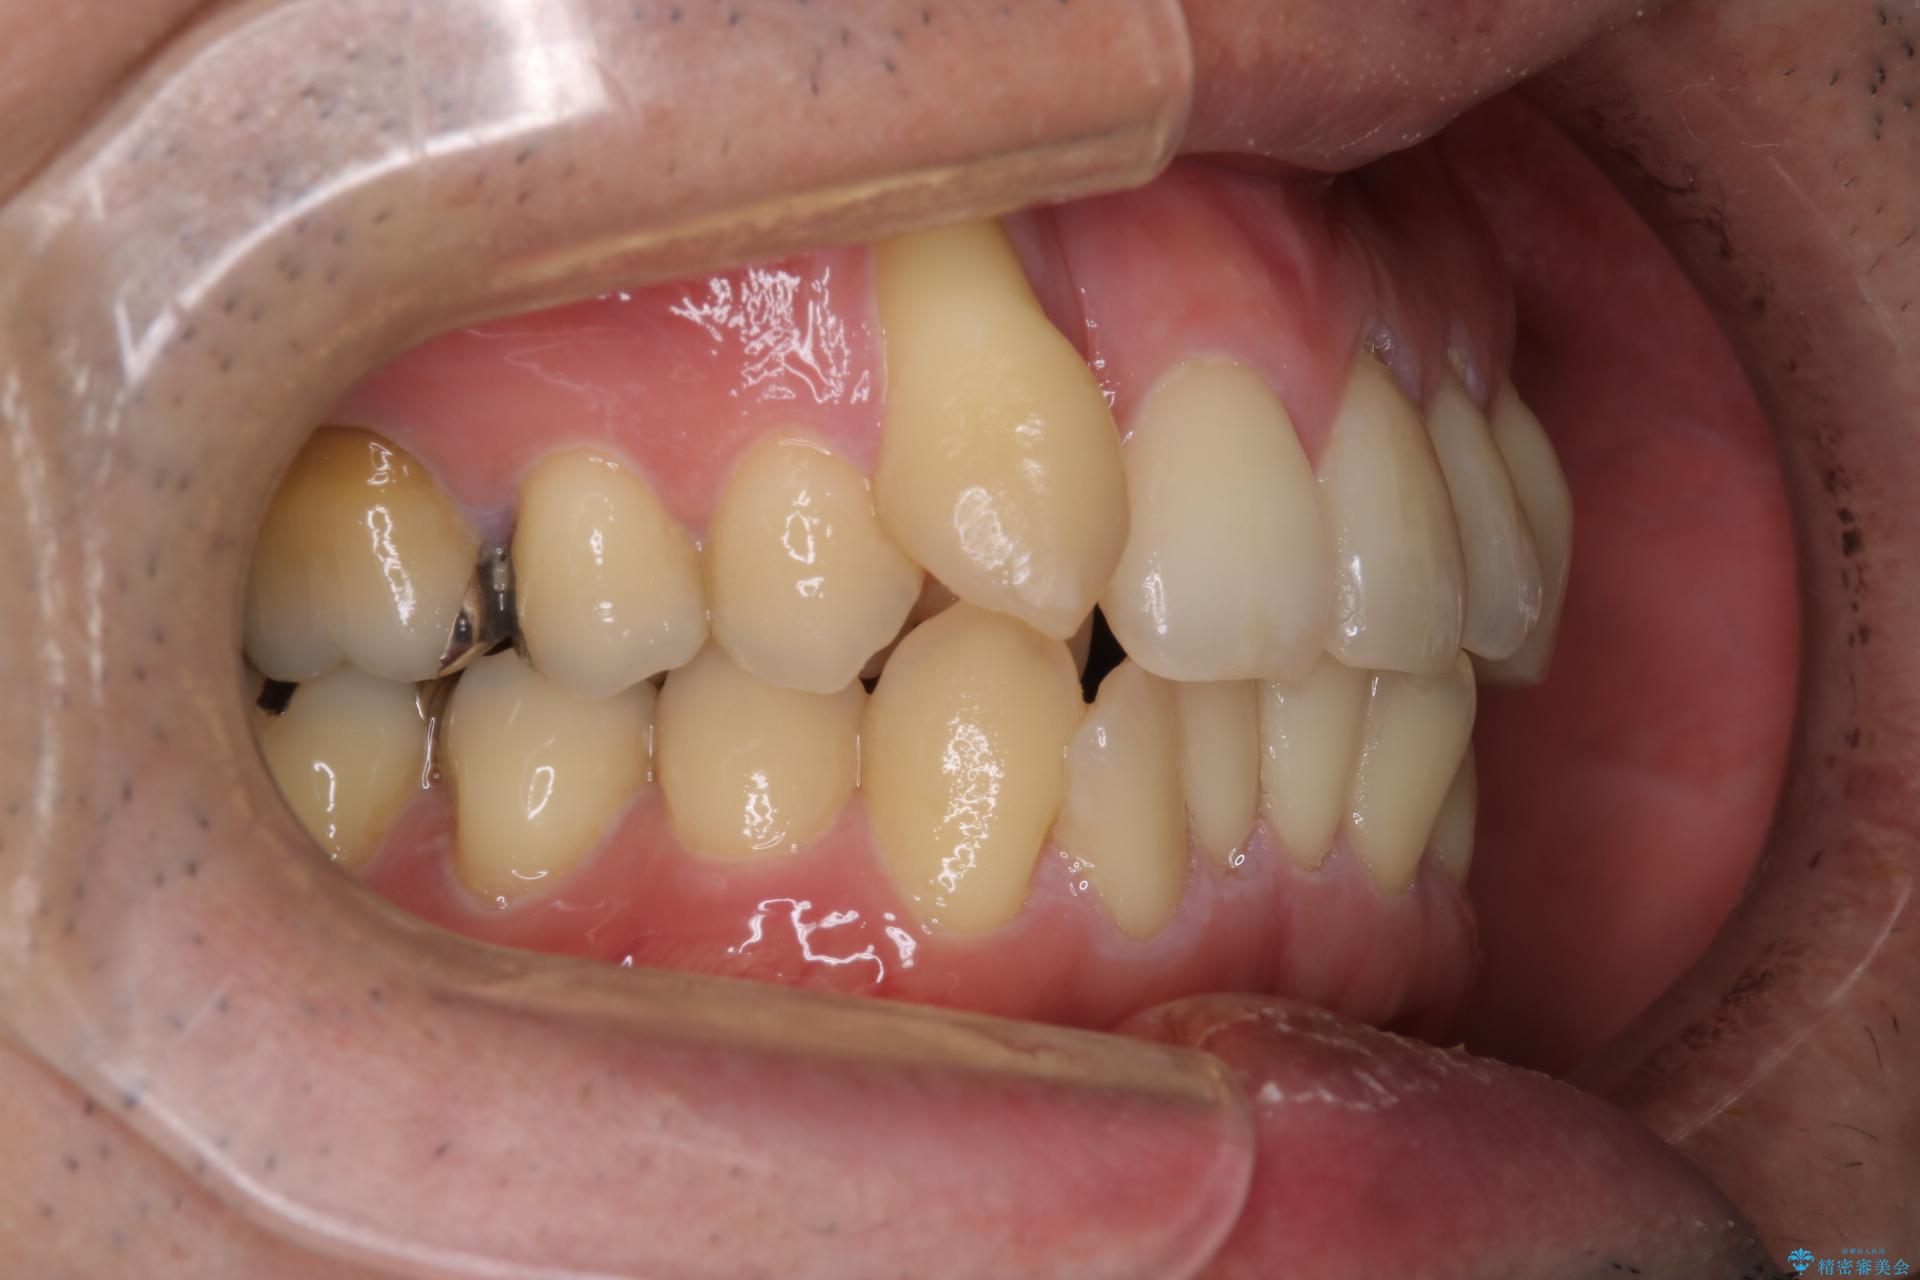

- 右上2番目の歯が舌側転位していることと前歯の叢生(がたつき)を主訴に来院されました。

右上の犬歯が初診時よりかなり歯根露出しており、矯正の力をかけるとさらに歯根露出するリスクがあるため、右上の2番目の歯を前に出すためにも

右上の犬歯を抜歯して歯並びを整える治療計画を立てました。